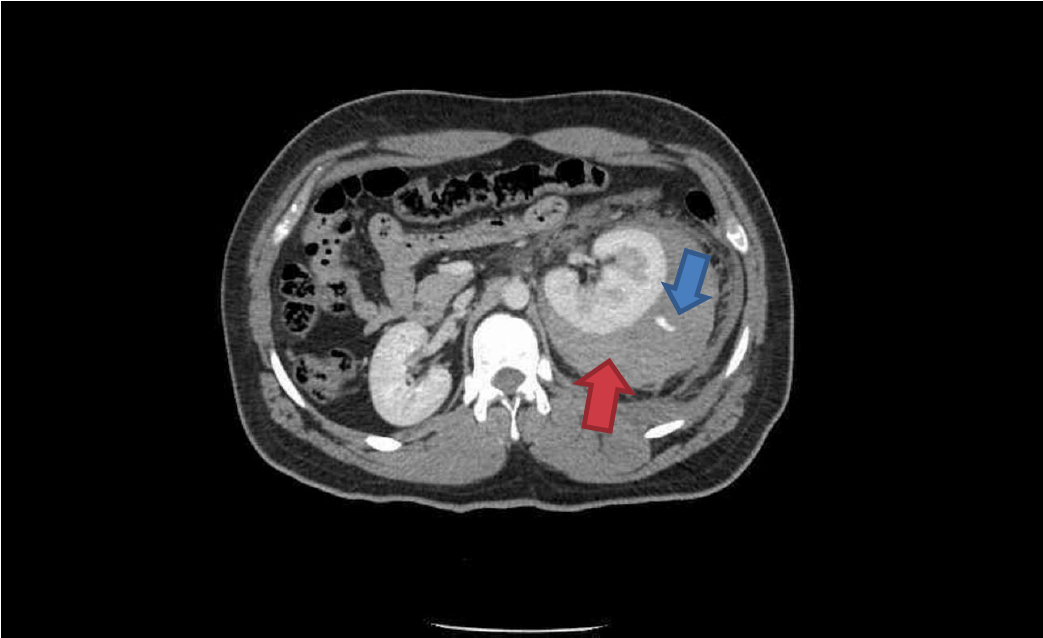

Trauma CT: Blue arrow is contrast ‘blush’=active bleeding point. Red arrow is perinephric haematoma.